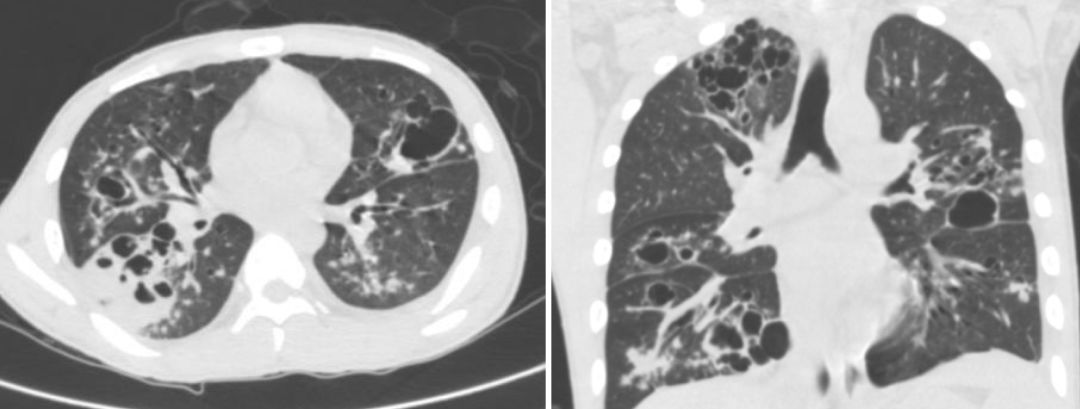

流感病毒相关细菌性肺炎与所谓的社区获得性肺炎的病原菌不同,以金黄色葡萄球、肺炎链球菌和流感嗜血杆菌等最为常见 [7, 9]。特别是合并金黄色葡萄球菌感染,是流感病毒肺炎的一个显著的特点 [10]。胸片表现为肺部炎性渗出影,病变进展迅速,短期内可形成肺脓肿、肺空洞、脓胸和肺气囊,实变区内见蜂窝样或虫蚀样改变(图5-6)。血源性金葡菌肺炎常继发于金葡菌败血症,一般为双肺多叶受累,病灶多位于外周 [13]。目前认为金葡菌所具有的细菌性蛋白酶可促进流感病毒表面蛋白血凝素的开裂,促进病毒活化和复制,增强其感染性和致病能力 [7, 9]。临床表现危重,如果治疗不及时,死亡率高达42%[14]。

(图5、图6)